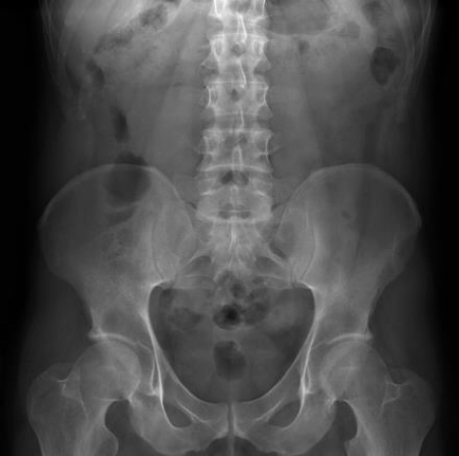

What is this abdominal x-ray showing?